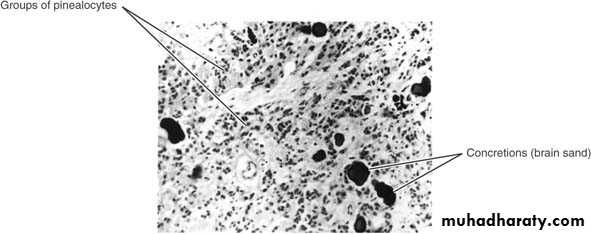

- consist of pinealocytes and the glial cells

- Calcifications may be found normally at age of 16

- cysts may be found (pineal cyst)

Photomicrograph of a section of the pineal gland stained with hematoxylin and eosin